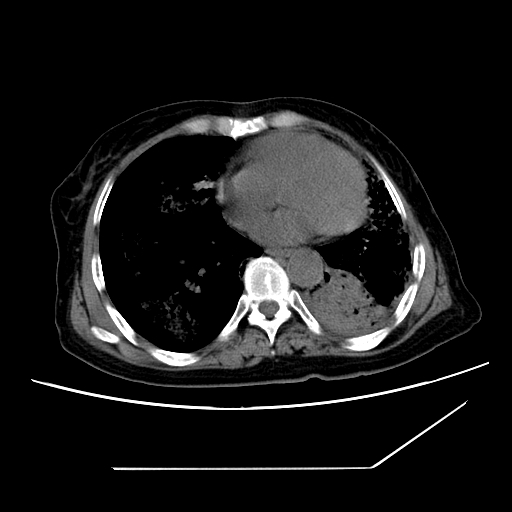

标题: CT25393:病人45岁,咳嗽,吐黄痰带血丝,发热,胸闷月余 [打印本页]

标题: CT25393:病人45岁,咳嗽,吐黄痰带血丝,发热,胸闷月余

1、左肺中央型肺癌并双肺弥漫性转移   2、双肺部感染    3、肺大泡     4、左侧胸腔积液

双侧肺弥漫性病变,可见“空泡征”及“蜂窝征”,考虑肺泡癌可能性大,左侧胸腔积液,考虑胸膜受累可能!

1)不排除肺泡癌可能。2)左侧胸腔积液。